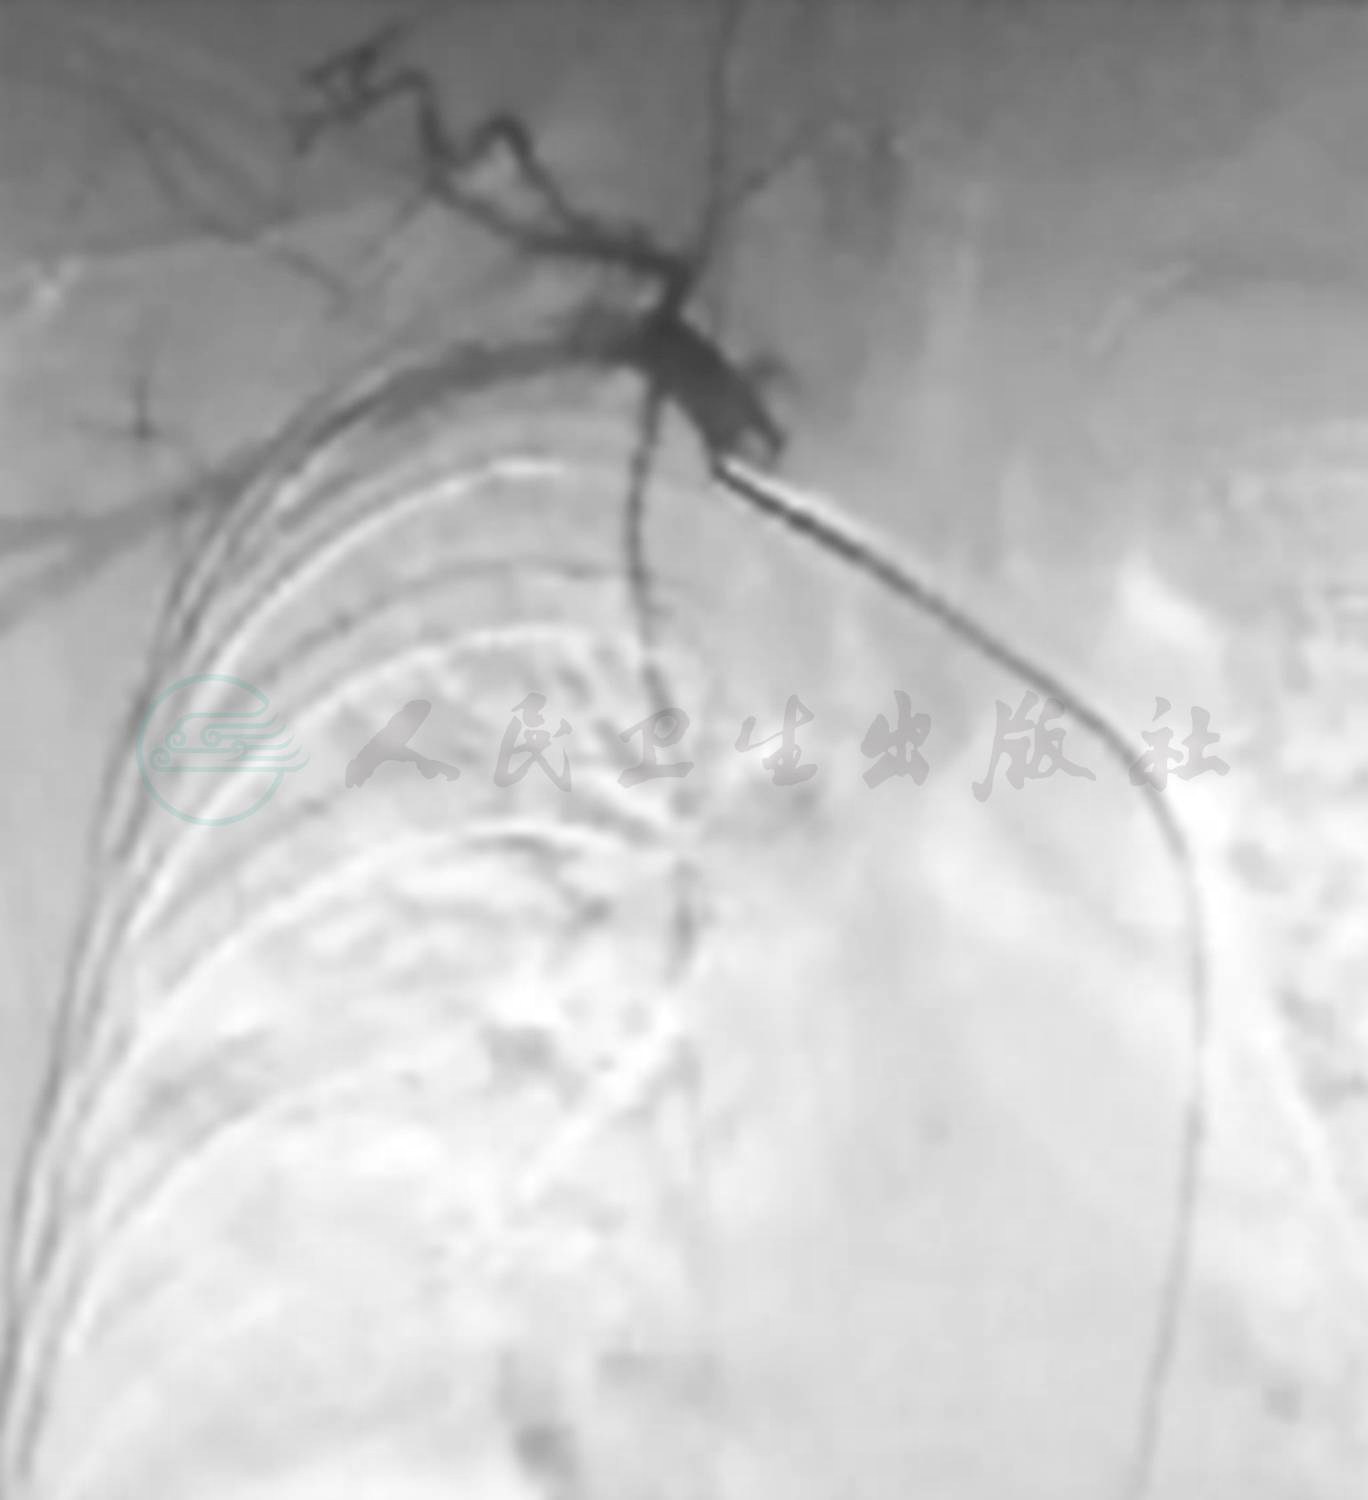

入院后急检血常规白细胞正常范围,予患儿头孢甲肟预防感染,同时完善病原学及相关常规检查。次日回报TB-Ab阴性;结核抗体阴性,肺炎衣原体抗体-IgM 阴性;肺炎支原体抗体-IgM 阴性,暂无结核、肺炎支原体及衣原体感染的证据;血红蛋白92g/L,提示轻度贫血。抗核抗体、抗nRNP抗体、抗Sm抗体、抗SS-A抗体、抗dsDNA抗体均阴性;抗线粒体抗体均为阴性;抗心磷脂抗体(ACA)、抗中性粒细胞胞质抗体测定(ANCA)及抗核抗体系列(ANA)均阴性,暂不支持系统性红斑狼疮等结缔组织病和ANCA相关性血管炎等引起的肺部损害。心电图正常,心脏超声正常不支持心源性咯血。入院第2天患儿再次咯血,量同前,检查血常规提示血红蛋白进行性下降提示肺部进行性出血,立即予患儿行支气管镜检查以明确出血部位,术中发现右肺下叶基底段可见鲜血涌出(图1),予1/10 000盐酸肾上腺素局部止血。因患儿出血量较大并急行肺部增强CT扫描提示:右肺中下叶见磨玻璃密度斑片影(图2),不除外肺血管异常导致出血,立即请介入科会诊,予患儿行支气管动脉造影术,术中发现血管略增粗扭曲,另见血管瘘(图3),予明胶海绵填塞后支气管动脉栓塞良好(图4)。夜间患儿再次出现呕血1次,约为50ml鲜血,患儿血氧饱和度下降,予患儿低流量吸氧,并予患儿垂体后叶素持续静脉滴注,联合凝血酶及酚磺乙胺止血并积极补液输血纠正贫血治疗。肺灌洗液结核菌涂片阴性,PPD阴性,结合支气管镜下的改变可除外肺结核;肺泡灌洗液未查到含铁血黄素细胞不支持肺含铁血黄素沉着症。患儿共住院治疗1周,无发热,未再次咯血及活动性出血表现出院观察。出院后电话随诊,患儿出院后无再次咯血,无反复感染及咳嗽史。

图4 透视下缓慢注入明胶海绵与少量造影剂的混悬液,再次造影见该支气管动脉栓塞良好